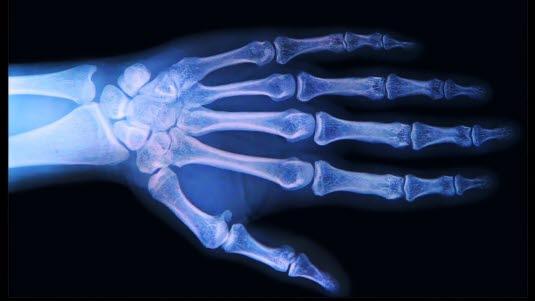

Røntgen av ledd

Røntgen av ledd fremstiller beinvevet i og rundt ledd i skjelettet. Brusk, leddhinne (synovium), leddvæske, leddkapsel og leddbånd lar seg ikke direkte fremstille på røntgen. Den vanligste sykdommen i leddene er artrose. Årsaken til artrose er som oftest høy alder, tidligere skade eller betennelse. Ved artrose vil brusken som dekker de to beinendene i leddet, bli tynnere. Det betyr at rommet mellom de to beinene i leddet, leddspalten, blir smalere. Andre slitasjeforandringer vil være kalkutfellinger, påleiringer, i og rundt leddet.

Undersøkelsen gjøres som en viktig del av utredningen av leddplager. Normale funn ved røntgen innebærer at skjelettstrukturer er normale, uten påleiringer og har normal bruskhøyde. Rønten av ledd kan også påvise hevelser i bløtvev, men til dette er f.eks. MR-undersøkelser mye bedre egnet.

En lang rekke forandringer kan påvises. Tegn på leddbetennelse (artritt) er smalere eller trangere leddspalte, hevelse i bløtvevet rundt leddet og leddnær beinskjørhet. Tegn på artrose er forkalkninger i og rundt leddet, små beinutvekster og små blæredannelser i beinet, og i langtkomne tilfeller endres leddets form.

Leddgikt gir typisk forandringer i de små leddene i fingre og tær, samt i håndleddene. Store ledd kan angripes lengre ut i forløpet. Artrose i hendene rammer de ytterste leddene i fingrene, men hofter og knær er de mest utsatte og plagsomme former for artrose. Urinsyregikt (podagra) kommer nesten alltid i stortåens grunnledd.